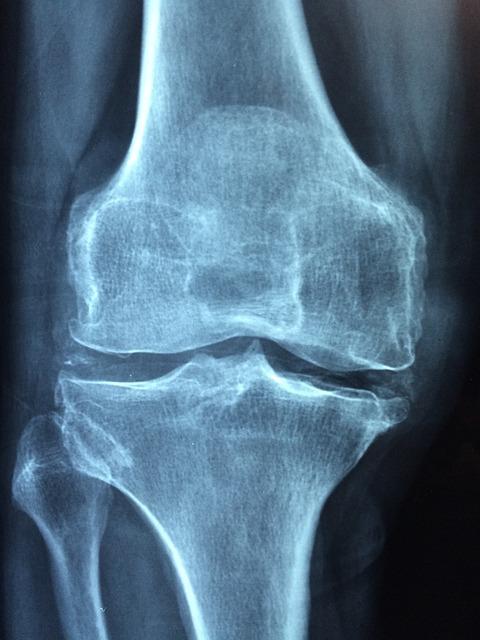

</table><br/><img class="kimage_class" src="https://www.beechmontsoccerclub.com/wp-content/uploads/2024/02/g749e07c043a4aa946b9355190c313ba2b73638d284d5ffc4b831996eb1bc234c83483ad62eec3e4d4c0c63e5285066abb3b2cd81dade7f0fdb6b4ebca4e16d17_640.jpg" alt="Surgical Interventions for a Torn Meniscus: Exploring Your Options"><br/><h2 id="surgical-interventions-for-a-torn-meniscus-exploring-your-options">Surgical Interventions for a Torn Meniscus: Exploring Your Options</h2>Surgical interventions are often recommended for individuals suffering from a torn meniscus, a common knee injury. If you're an avid soccer player dealing with this condition, you may be wondering whether it's still possible to continue enjoying your favorite sport. While it's always best to consult with a medical professional for personalized advice, exploring your surgical intervention options can help you make an informed decision about resuming soccer activities.